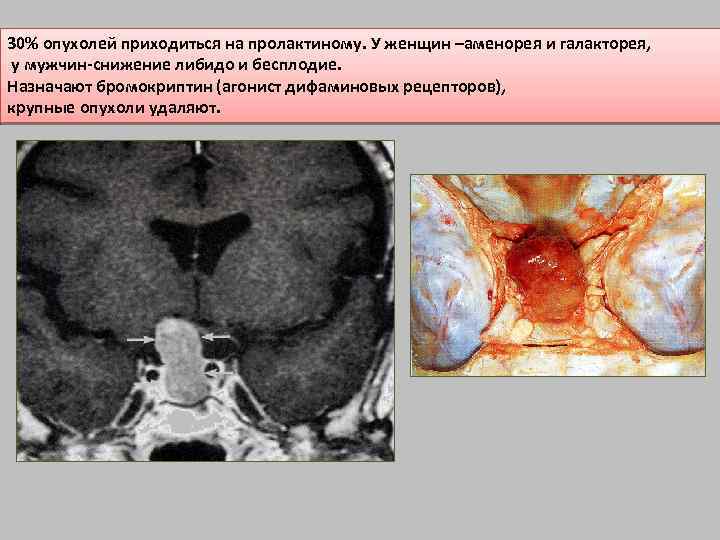

30% опухолей приходиться на пролактиному. У женщин –аменорея и галакторея, у мужчин-снижение либидо и бесплодие. Назначают бромокриптин (агонист дифаминовых рецепторов), крупные опухоли удаляют.